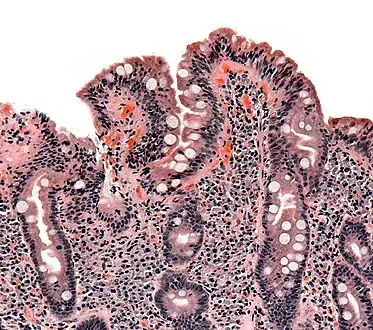

| Biopsy of small bowel showing coeliac disease manifested by blunting of villi, crypt hypertrophy, and lymphocyte infiltration of crypts | |

The classic pathology changes of coeliac disease in the small bowel are categorised by the "Marsh classification":[99]

- Marsh stage 0: normal mucosa

- Marsh stage 1: increased number of intra-epithelial lymphocytes (IELs), usually exceeding 20 per 100 enterocytes

- Marsh stage 2: proliferation of the crypts of Lieberkühn

- Marsh stage 3: partial or complete villous atrophy and crypt hypertrophy[100]

- Marsh stage 4: hypoplasia of the small intestine architecture